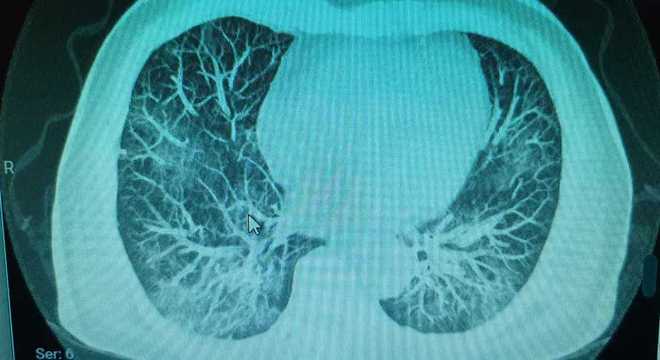

Streptococcus pneumoniae (j13) is the most common bacterial cause of pneumonia in all age groups except. It is considered the only acute process. Individualization of a clinicopathologic entity in a series of 12 patients. A segunda mais comum em termos de bactérias; La neumonía adquirida en la atención médica es una infección bacteriana que se produce en personas que viven en centros de atención a largo plazo o que reciben atención en clínicas ambulatorias. Bacterial pneumonia is an infection of your lungs caused by certain bacteria. Histologic features and clinical significance. No tratamento da pneumonia bacteriana grave, que surge principalmente em indivíduos com hiv o diagnóstico da pneumonia é confirmado por exames de radiografia ou tomografia do tórax.

Pneumonia este o inflamație a țesutului pulmonar, de obicei cauzată de o infecție virală sau bacteriană. Fatores de risco para desenvolver a infecção: Bacterial pneumonia is characterized by exudative solidification (consolidation) of the pulmonary tissue, which is caused by bacterial invasion of the lung parenchyma. Tomografia computadorizada por raios x. Haemophilus influenzae type b (hib): Individualization of a clinicopathologic entity in a series of 12 patients. Pneumonia can be generally defined as an infection of the lung parenchyma, in which consolidation of the sections bacterial pneumonia. Bacterial pneumonia is an infection of your lungs caused by certain bacteria. Icc, doença renal crônica, diabetes, desnutrição, alcoolismo. Streptococcus pneumoniae (j13) is the most common bacterial cause of pneumonia in all age groups except. A segunda mais comum em termos de bactérias; A pneumonia é uma infecção aguda do pulmão. To describe hrct findings in patients with bacterial pneumonia.

O diagnóstico da pneumonia bacteriana pode ser feito por um clínico geral e/ou médico pneumologista através de exames, como raio x do tórax, tomografia computadorizada do tórax. Individualization of a clinicopathologic entity in a series of 12 patients. Bacterial pneumonia is a type of pneumonia caused by bacterial infection. Tomografia computadorizada por raios x. A segunda mais comum em termos de bactérias;

O diagnóstico da pneumonia bacteriana pode ser feito por um clínico geral e/ou médico pneumologista através de exames, como raio x do tórax, tomografia computadorizada do tórax. A pneumonia é uma infecção aguda do pulmão. A segunda mais comum em termos de bactérias; To describe hrct findings in patients with bacterial pneumonia. Icc, doença renal crônica, diabetes, desnutrição, alcoolismo.